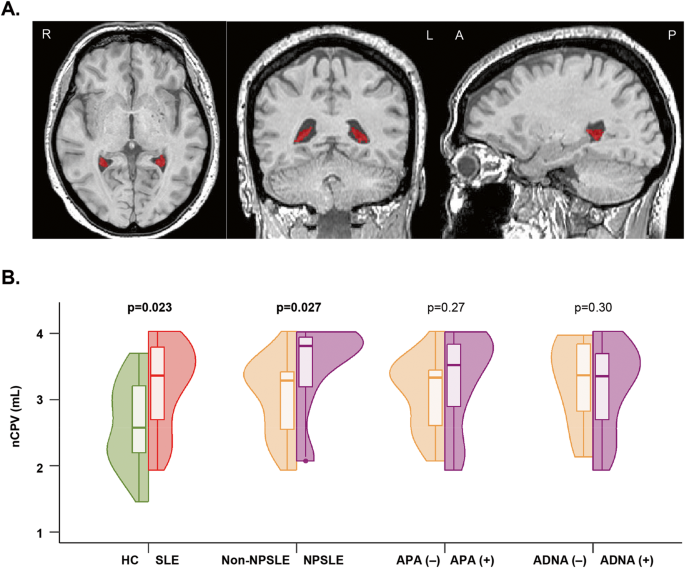

Choroid plexus and perivascular space enlargement in neuropsychiatric systemic lupus erythematosus

Choroid plexus (CP) enlargement is proposed as a marker of neuroinflammation in immune-mediated conditions. CP involvement...